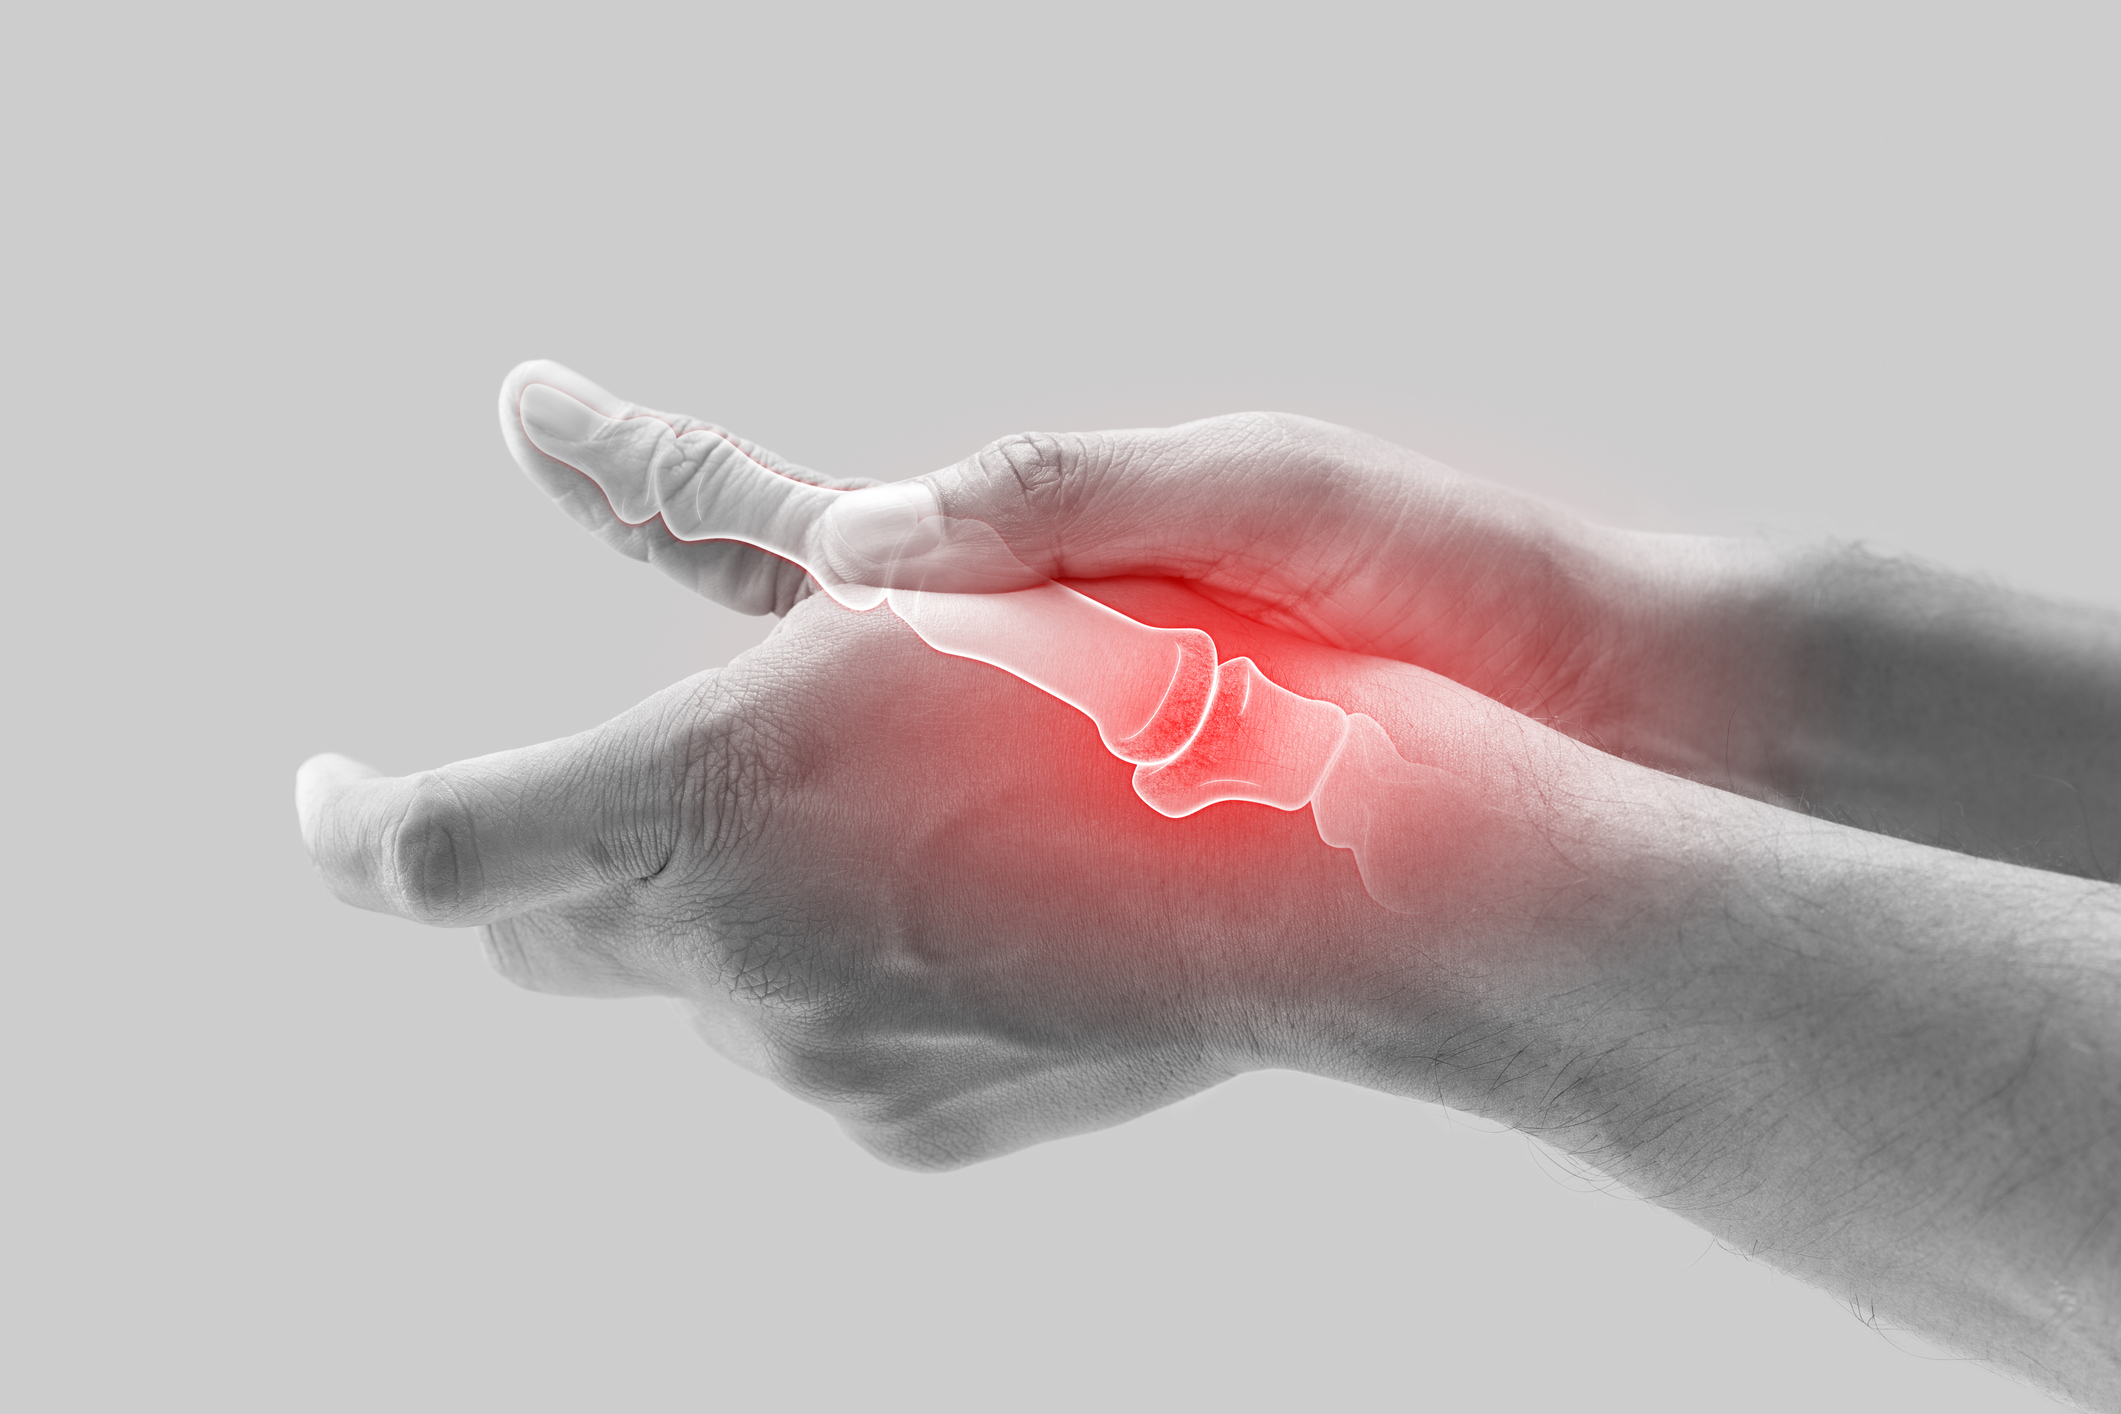

Unter dem Begriff Arthrose versteht man die Abnützung eines Gelenks. Sobald sich ein Gelenk einmal abgenützt hat, gibt es keine natürliche Heilung durch den Körper mehr – der betroffene Knorpel ist für immer verschwunden und kann sich nicht mehr neu bilden. Jedes Gelenk kann von einer Arthrose betroffen sein. Im Bereich der Hand ist die häufigste Form die Rhizarthrose. Hierbei ist das Daumensattelgelenk betroffen. Patienten/-innen klagen oftmals über starke Schmerzen, welche vor allem bei Belastung im Daumenbereich auftreten.

Leichtes Ziehen nach vermehrter Belastung bis hin zu starken Schmerzen in Ruhe am Übergang des Daumens zum Handgelenk (je nach Stadium der Erkrankung), Tastbare Erhabenheit, Bewegungseinschränkung, Kraftverlust